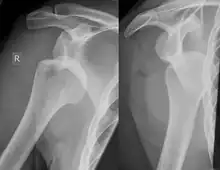

Diagnosis can be suspected by history and physical examination which is usually followed by imaging. Because of the mechanism of injury, apprehension of anterior dislocation is common with provocative maneuvers. Hill–Sachs lesions have been classified as "engaging" or "non-engaging", with engaging lesions defined by the ability of the glenoid to sublux into the humeral head defect during abduction and external rotation. Engaging dislocations have a higher risk of recurrent anterior dislocation, and their presence can help guide surgical management.[2] Imaging diagnosis conventionally begins with plain film radiography. Generally, anteroposterior (AP) radiographs of the shoulder with the arm in internal rotation offer the best yield while axillary views and AP radiographs with external rotation tend to obscure the defect. However, pain and tenderness in the injured joint make appropriate positioning difficult and in a recent study of plain film x-ray for Hill–Sachs lesions, the sensitivity was only about 20%. i.e. the finding was not visible on plain film x-ray about 80% of the time.[3]